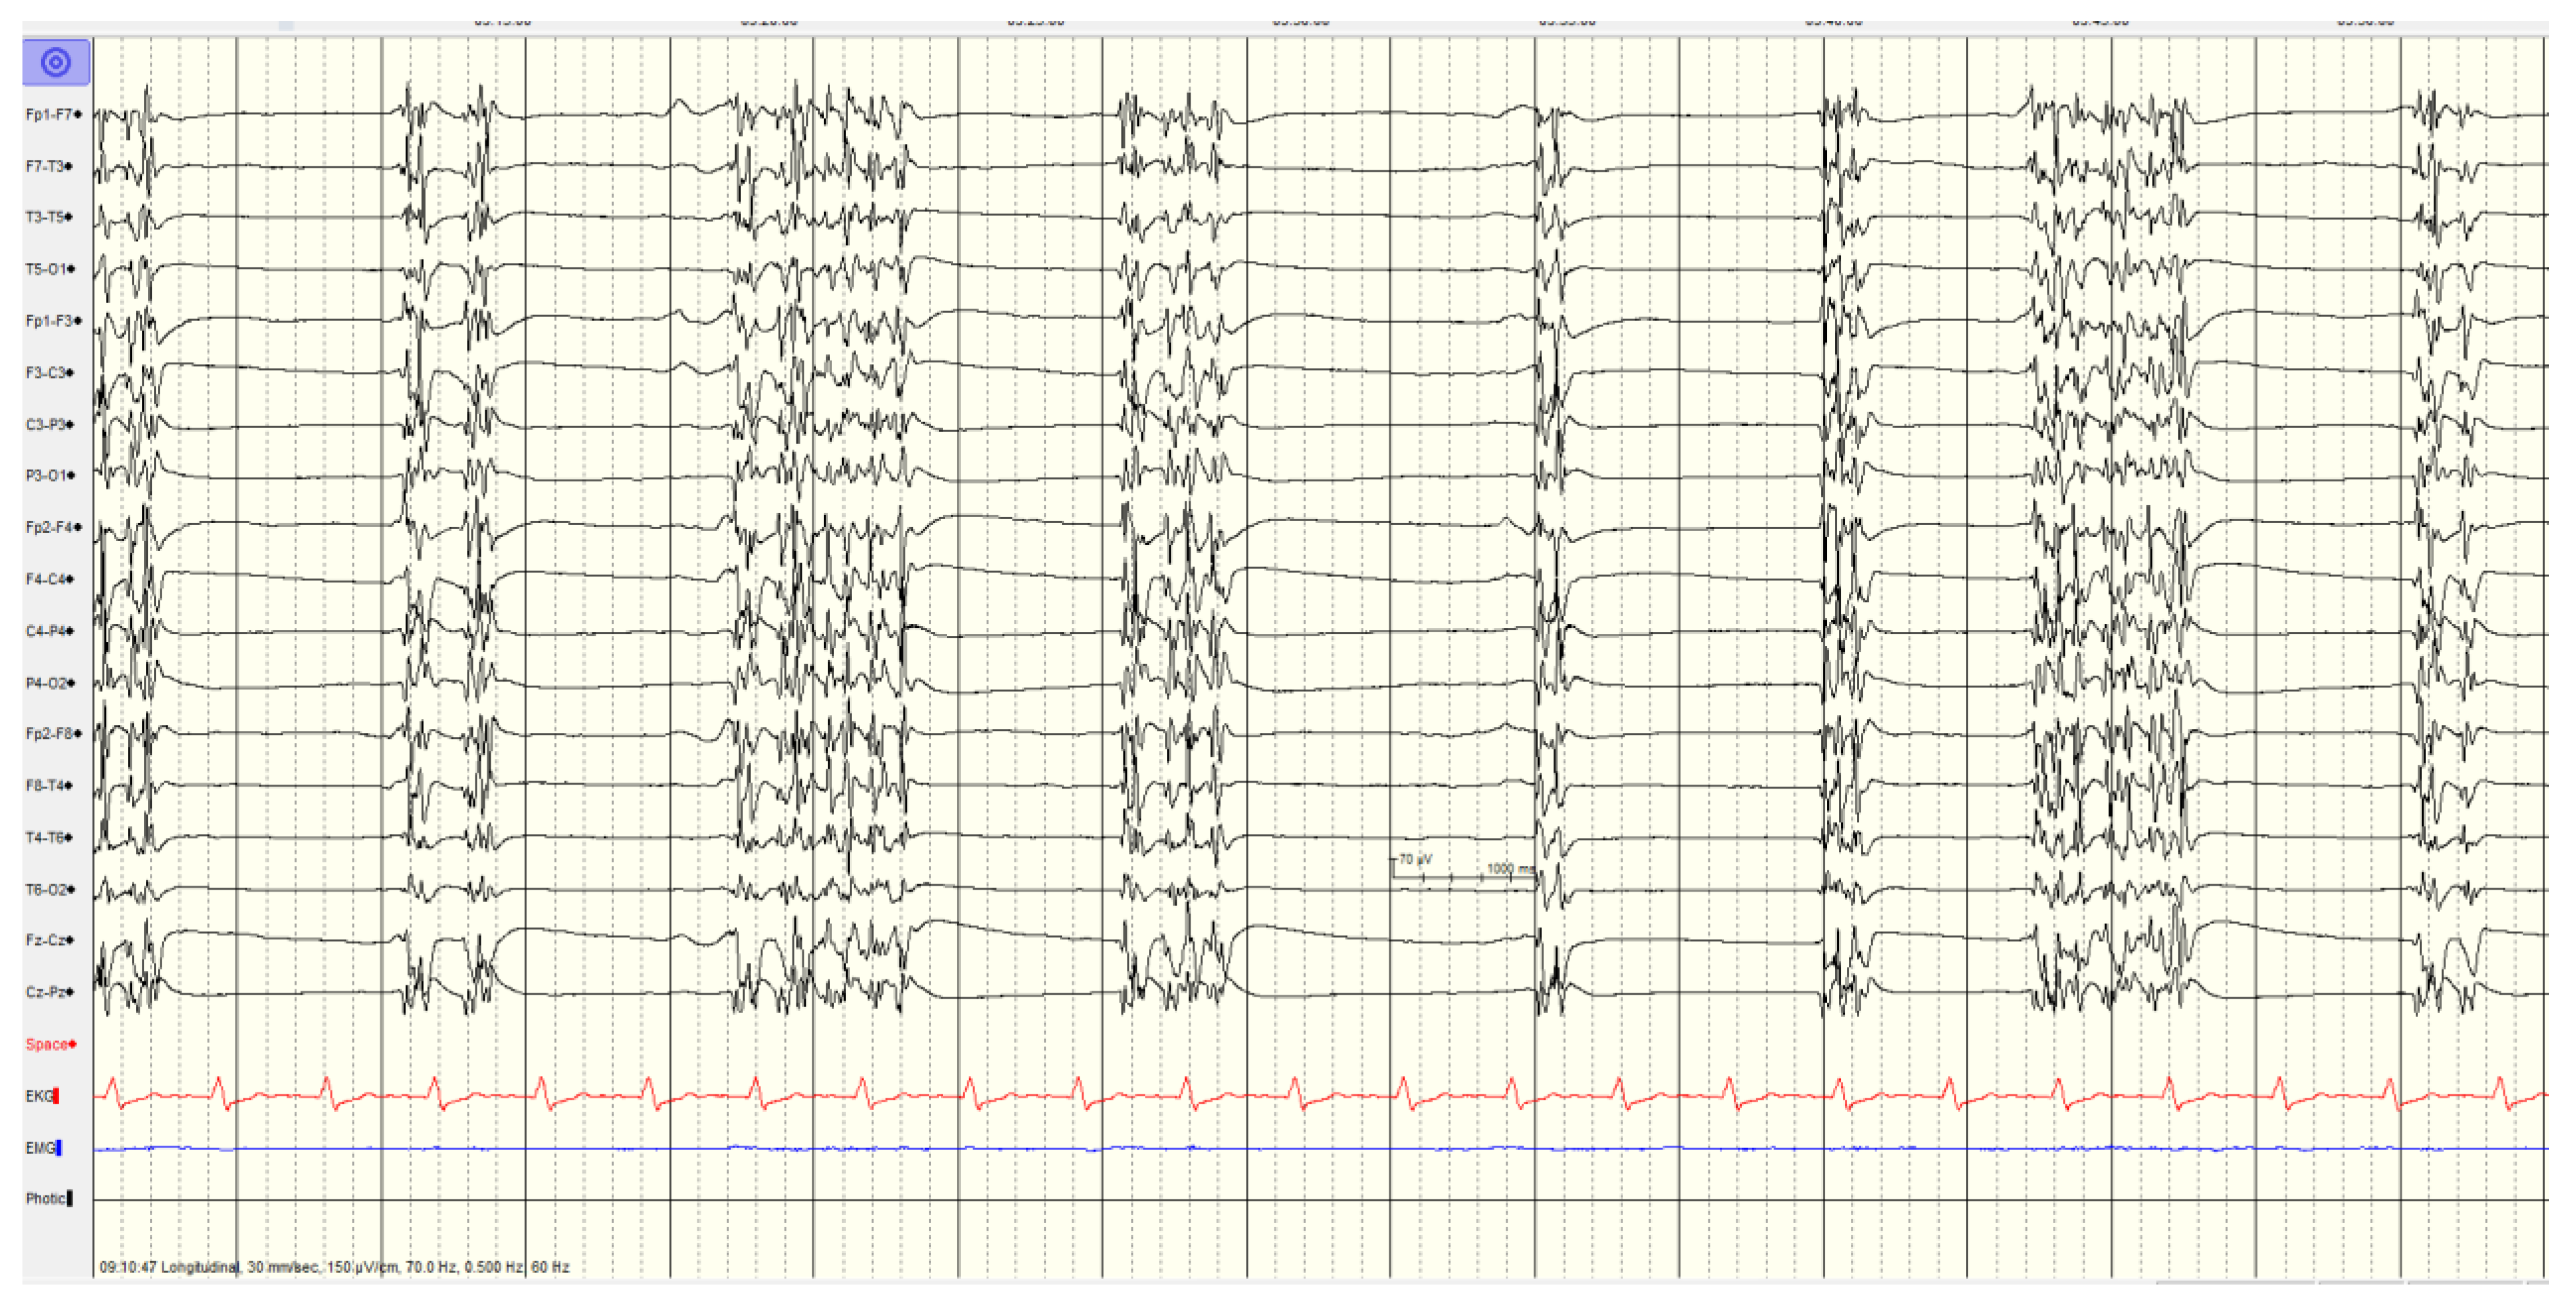

The specific EEG patterns classified into highly malignant (Figure 1, Figure 2 and Figure 3), malignant (Figure 4 and Figure 5) and benign and their relationship to outcomes are noted in Table 4.

Overall, 46 (57%) of patients showed a highly malignant EEG pattern (Figure 1, Figure 2 and Figure 3). None of these patients showed reactivity on EEG or improvement on a subsequent EEG when performed, and none in this category survived.

Figure 1. Highly malignant - Suppressed background with continuous periodic discharges.